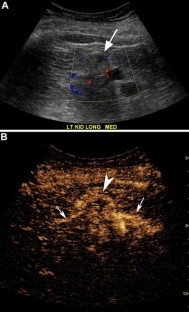

Fig. 1